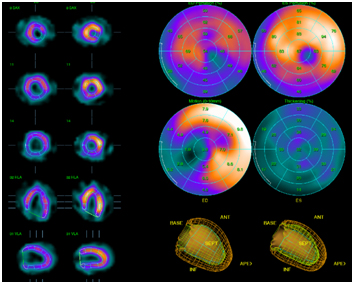

心臓カテーテル検査(冠動脈造影)にて狭窄や閉塞を確認した血管に対しては、バルーンやステントを用いて血管を広げて血流を確保します。

以前のバルーンやステント治療における再発率(内膜が増殖し再び狭くなる確率)は10-30%と報告されていましたが、近年の薬剤溶出性ステントの使用により再発率は数%にまで減少しています。また再発症例や小血管に対しては、薬剤溶出性バルーンを積極的に使用することにより留置するステントを減らすことに努めています。

心臓カテーテル 治療前 心臓カテーテル 治療後